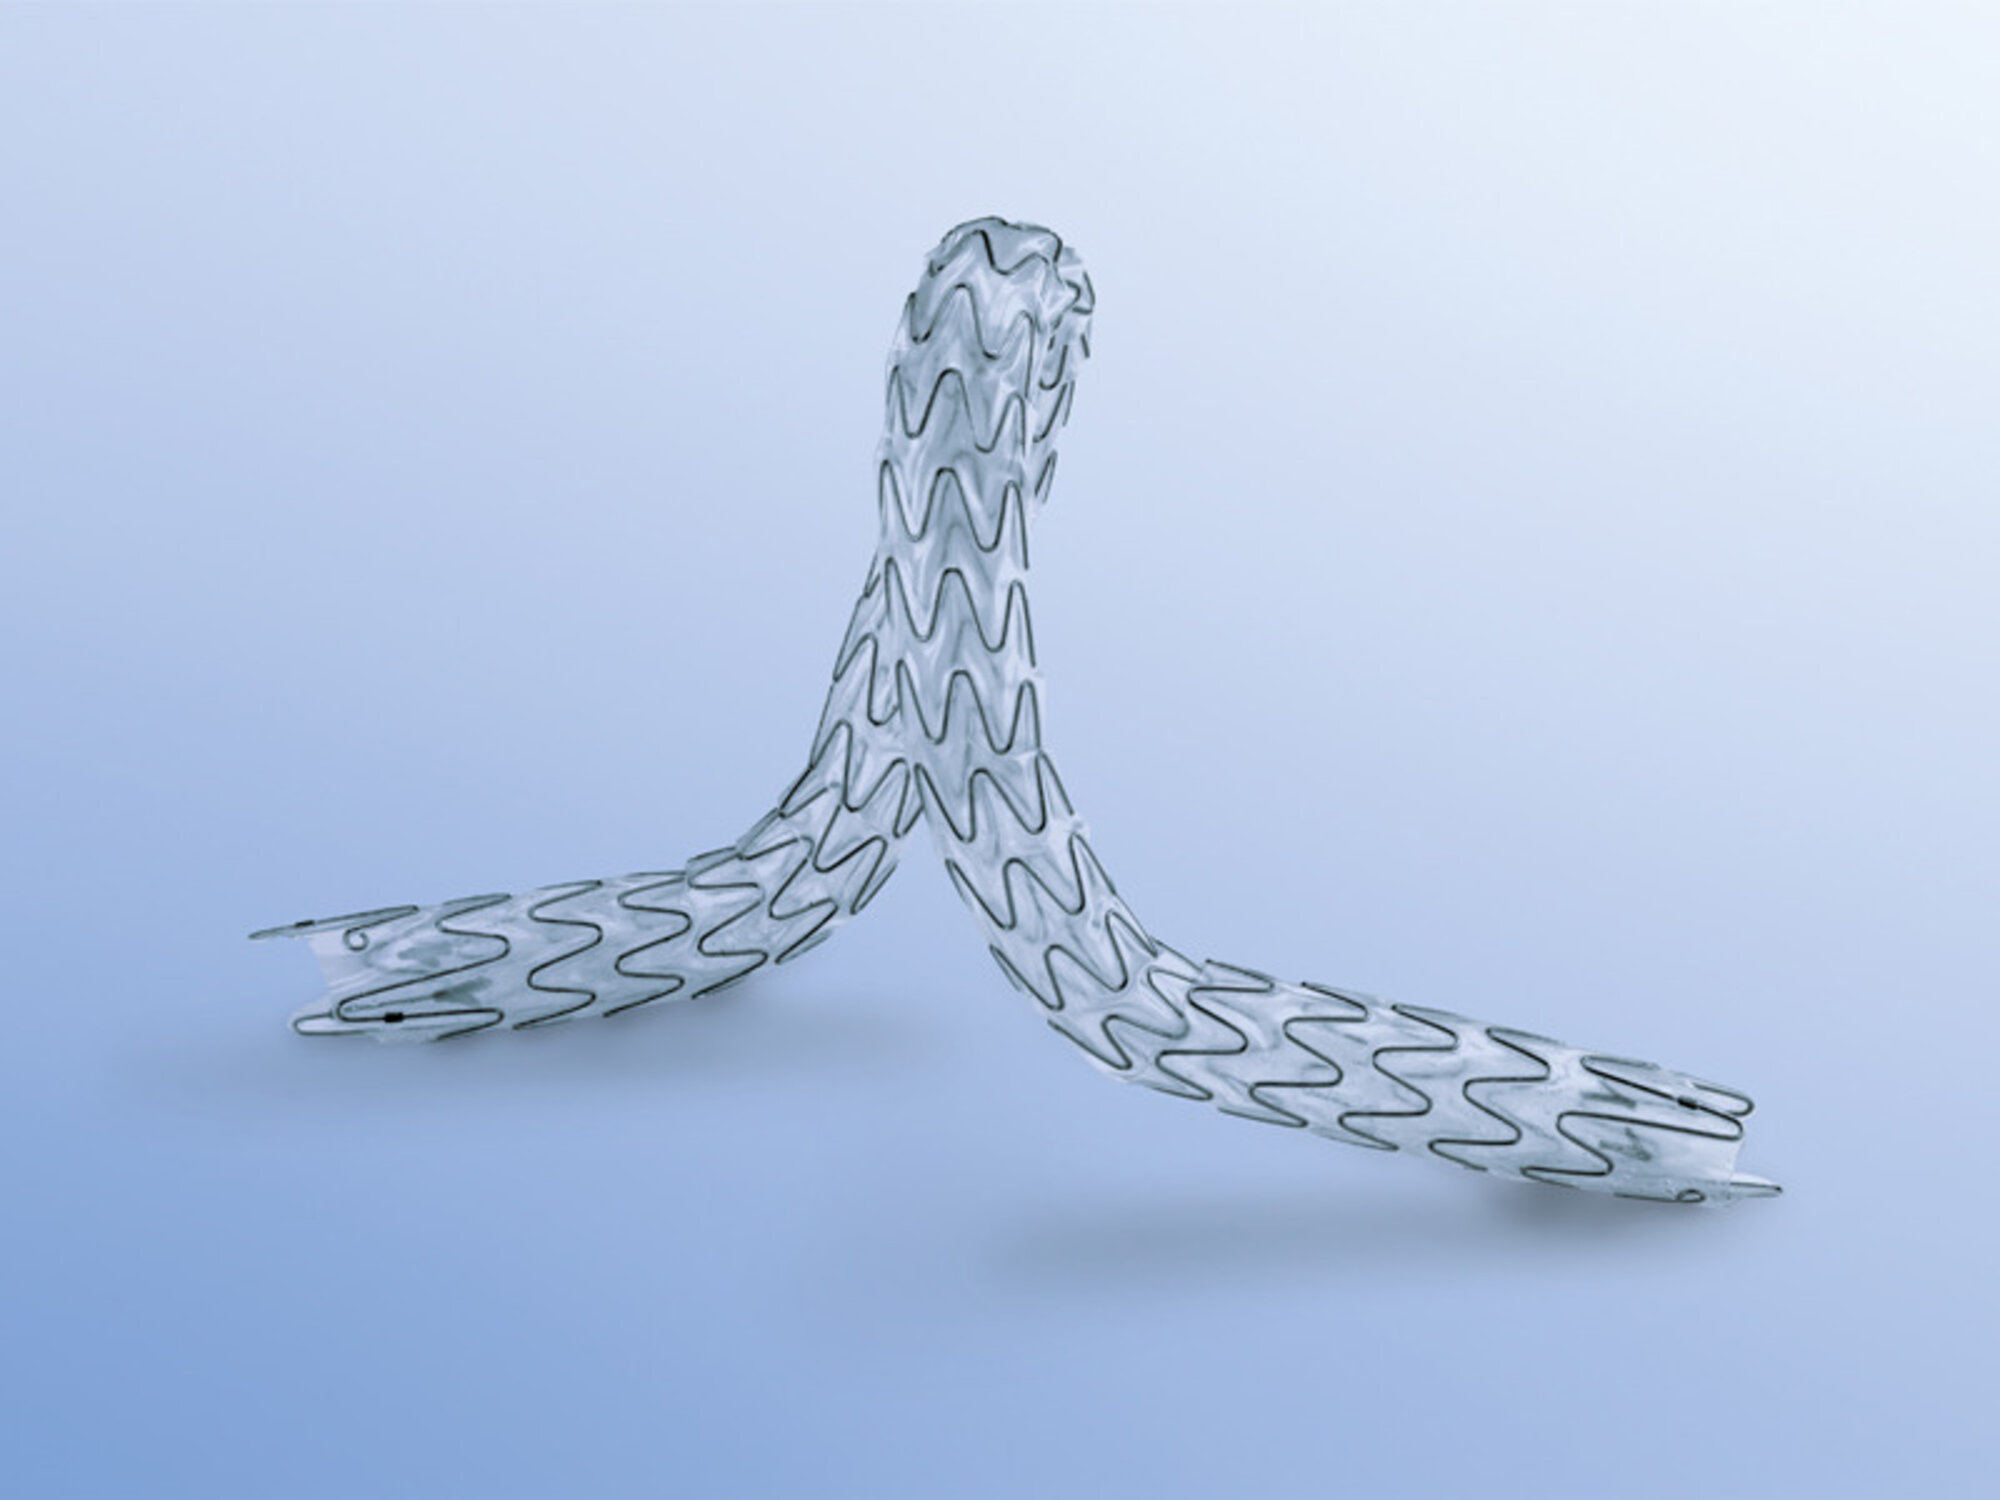

1. Ουρητηρική ενδοπρόθεση (URS) για Παλίνδρομη ή Ορθόδομη χρήση

2. Ενδοπρόθεση βολβικής ουρήθρας

3. Ενδοσκοπική τριγωνική ενδοπρόθεση (TPS) από Nitinol για προστατική ουρήθρα

4. Ενδοπρόθεση για στένωση του αυχένα της κύστης (RPS)

1. Ουρητηρική ενδοπρόθεση (URS) για Παλίνδρομη ή Ορθόδομη χρήση

2. Ενδοπρόθεση βολβικής ουρήθρας

3. Ενδοσκοπική τριγωνική ενδοπρόθεση (TPS) από Nitinol για προστατική ουρήθρα

4. Ενδοπρόθεση για στένωση του αυχένα της κύστης (RPS)